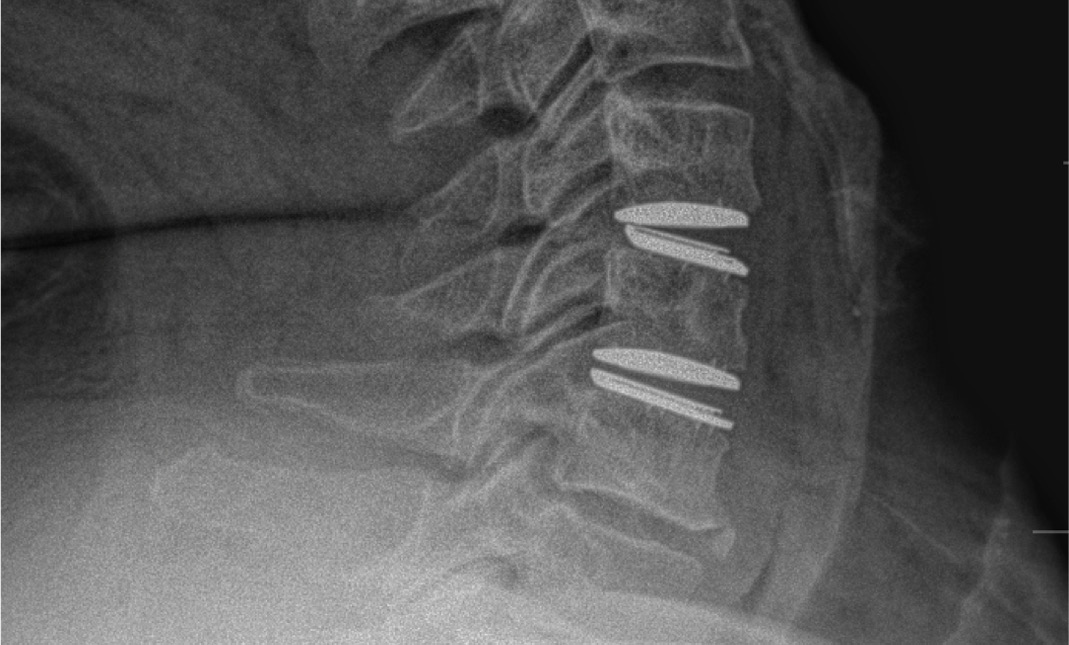

MRIs illustrated mild degenerative disc disease from C4-6 with disc herniations at both C4-5 and C5-6. The axial slice through C4-5 showed a right central disc herniation causing central and mainly right-sided foraminal stenosis. The axial slice through C5-6 showed a central disc herniation also causing central and mainly right-sided foraminal stenosis. The axial slice through C6-7 showed a left-sided disc herniation causing some left-sided foraminal stenosis, however, the patient did not demonstrate any left-sided symptoms.

Upon examination, the patient had good motion on flexion-extension, so fusion was not considered at all. My operative plan was to use prodisc cervical devices and replace both discs at C4-5 and C5-6, giving me the flexibility to use either a domed or flat implant.

During the procedure, prodisc C Vivo fit well within the C4-5 concave endplate. I expected to use a flat endplate prodisc C SK at C5-6, however I trialed the domed prodisc C Vivo and it actually looked good, so I unexpectedly used matching implants.

It was very helpful to have the flexibility to use either a flat or a domed implant at either level. Having the different size options available to truly match patient anatomy that the Match-the-Disc™ System provides enabled me to avoid having to alter the patient’s anatomy to fit the device.